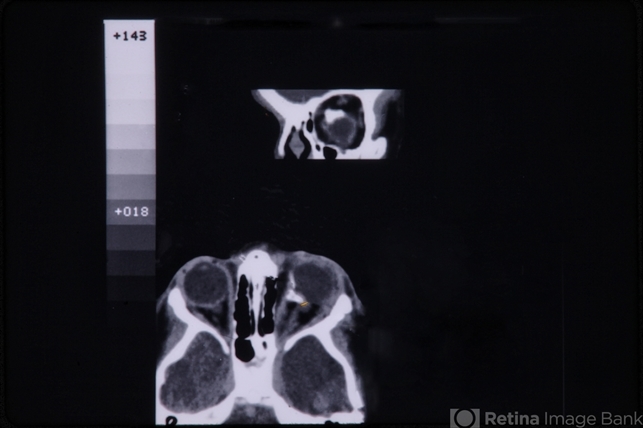

- linear nevus sebaceous syndrome, CT scan

- CT scan of linear nevus sebaceous syndrome.